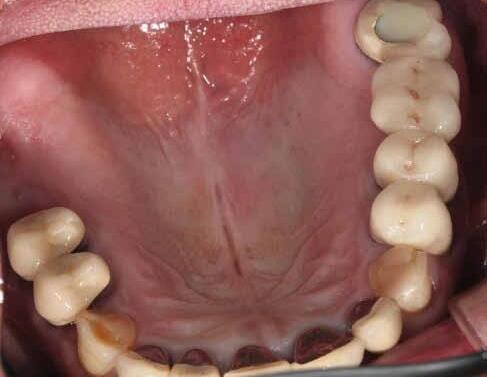

Fig 1. Patient anterior situation. Two anterior crowns fractured off.

Fig 3. Provisional restorations on central incisors and gingival images. The gingival contours were optimal, and the gingival phenotype was thick.